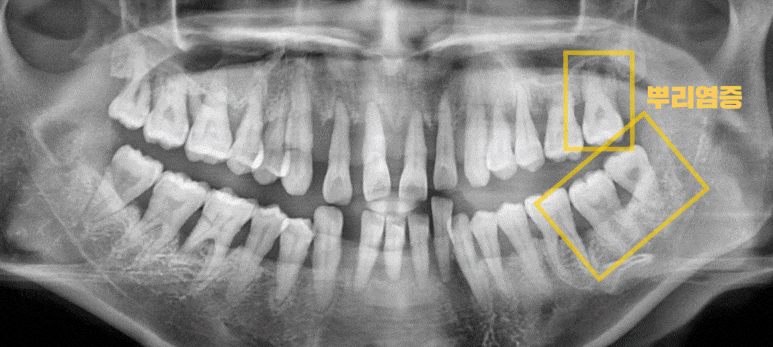

진단

낙성대역 치과

뿌리(치경부) 드러남

곳곳에 쌓여 있는 치석

잇몸(치은) 퇴축

염증으로 인한 부종

심한 흔들림(동요)

치근단염

위 문제점들을 찾을 수 있었습니다.

아무래도 앞쪽에 있는 전치부 치아들은 살릴 수 있는 게 거의 없어 보였는데요.

심한 흔들림이 나타나 금방이라도 빠질 것 같았습니다.

이와 더불어 좌측 어금니 3곳에서 충치로 인한 치근단염이 관찰되었습니다.

맨 안쪽에 있는 치아는 바로 빠져도 이상하지 않을 만큼 겨우 매달려 있었는데요.